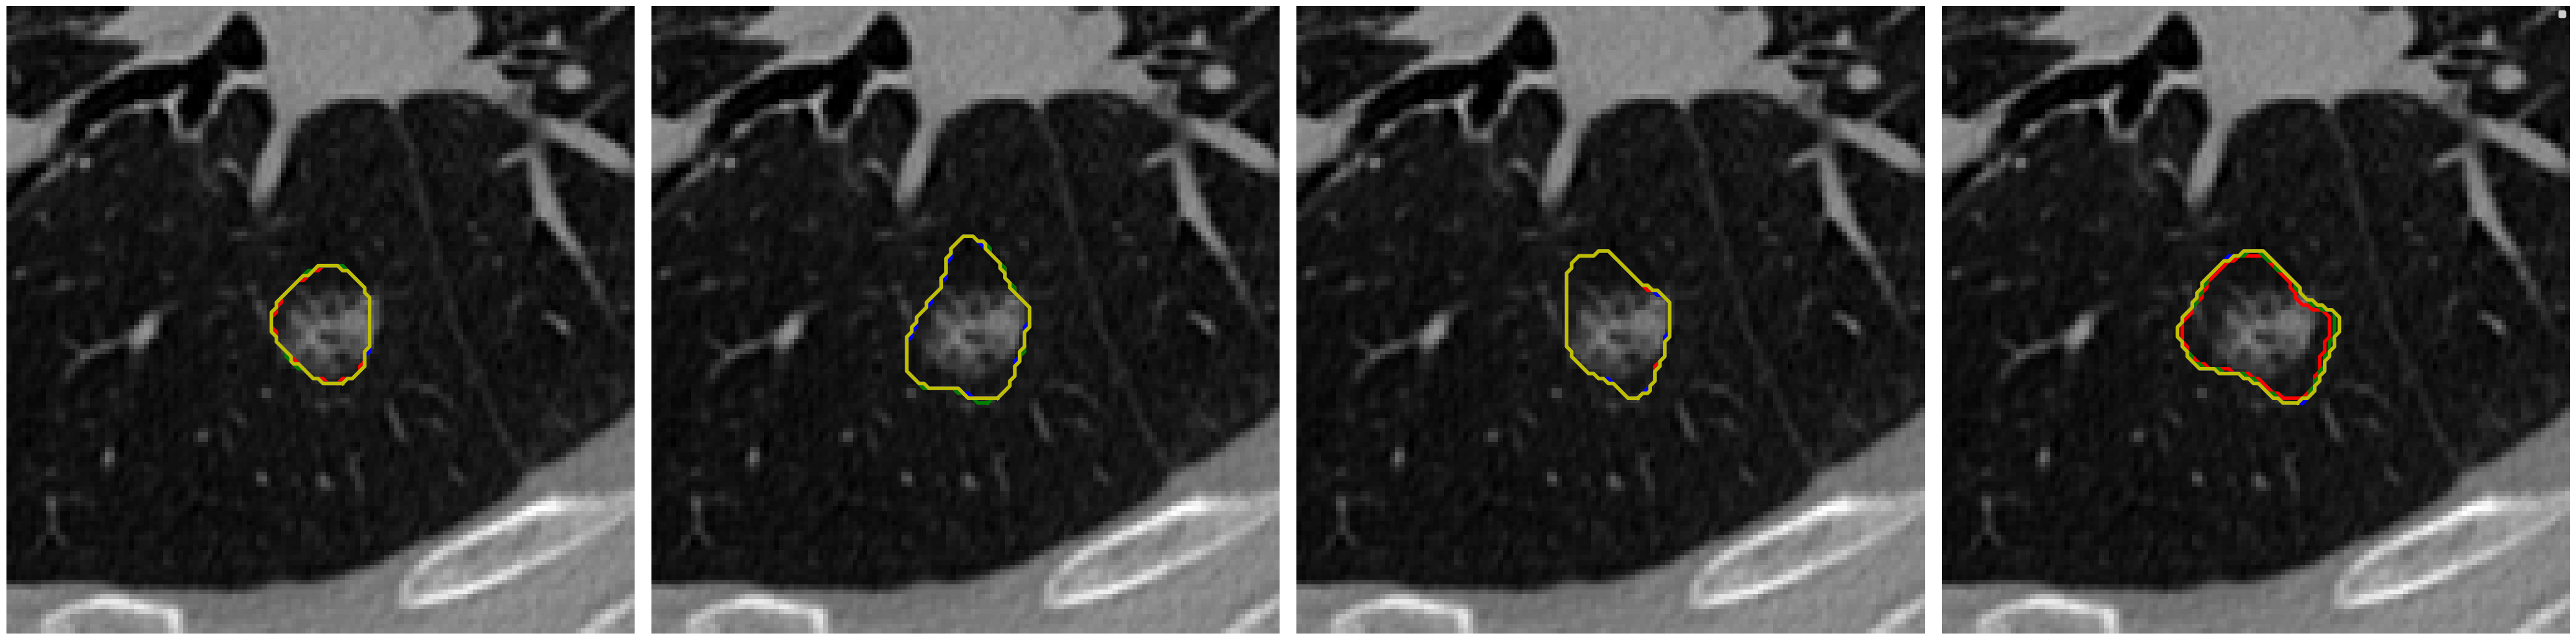

Visual comparison of segmentation results.

We provide visual comparisons of the segmentation results of all methods on the NPC dataset in Fig. 9 and Fig. 10, where different colors indicate the segmentation is obtained by different expert annotators. The segmentation results of ProSeg are more diverse and personalized than those of other methods. The segmentation results of ProSeg are more consistent with the ground truth while maintaining diversity among the generated segmentations. The results demonstrate that ProSeg effectively captures expert-specific characteristics and generates diverse segmentation results. For some methods, the segmentation from all the experts is the same, which means the diversity is poor. In Fig. 6(b), the second row shows the segmentation from our ProSeg, the third row shows the segmentation from the DPersona (stage 1) and the fourth row shows the segmentation from the DPersona (stage 2). For the second image, in the gold standard, three experts give segmentation containing two separate parts. Our ProSeg captures the character, while other models can hardly capture this difference, and generation methods can not tell which expert gives the two-part segmentation as shown in the figure that the color of the two-part segmentation is different from the Gold standard.